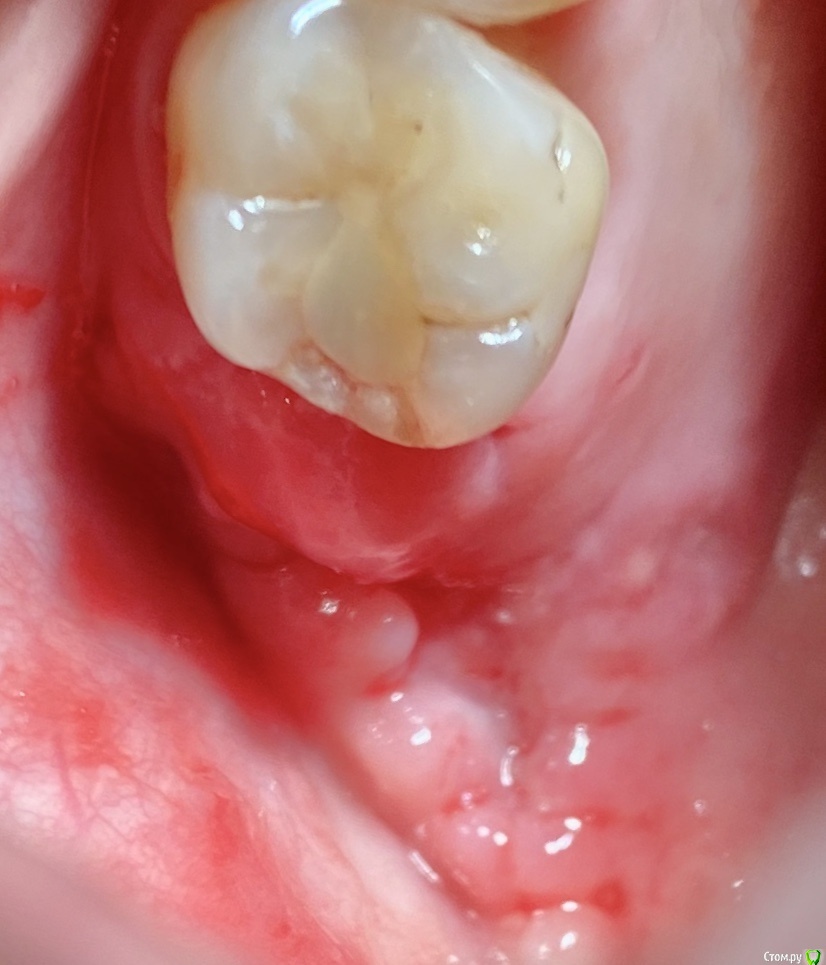

колесников Опубликовано 11 сентября, 2020 Поделиться Опубликовано 11 сентября, 2020 Перемещение бугра для закрытия лунки. Вестибулярно прикрепленную не смещаем. Вестибулярно компактной пластинки нет 9 Ссылка на комментарий

колесников Опубликовано 27 сентября, 2020 Поделиться Опубликовано 27 сентября, 2020 Вид через 2 недели Ссылка на комментарий